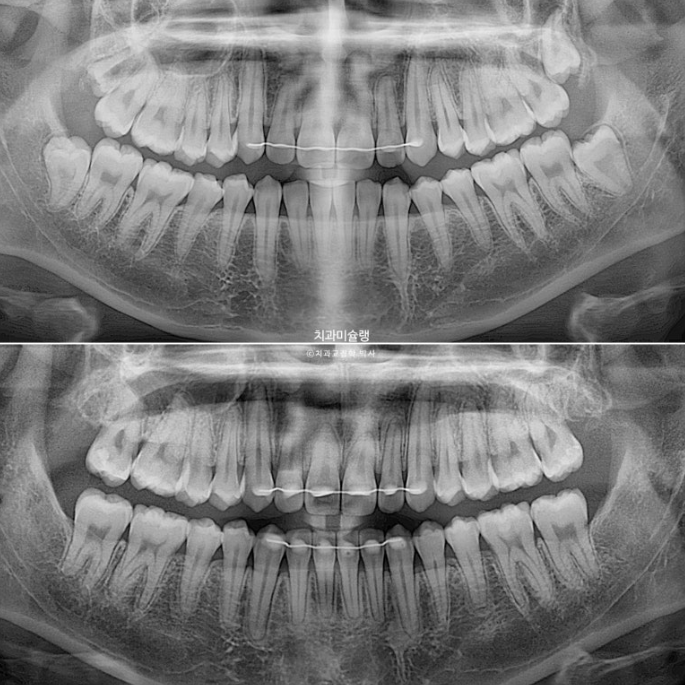

23.09~25.7

위 앞니에 초진시 이전 교정에 의한 치근흡수가 꽤 있는 상태였는데

이번 1년 10개월의 재교정 치료 기간동안 더 심해지지는 않았습니다.

치근 평행도는 좋습니다.